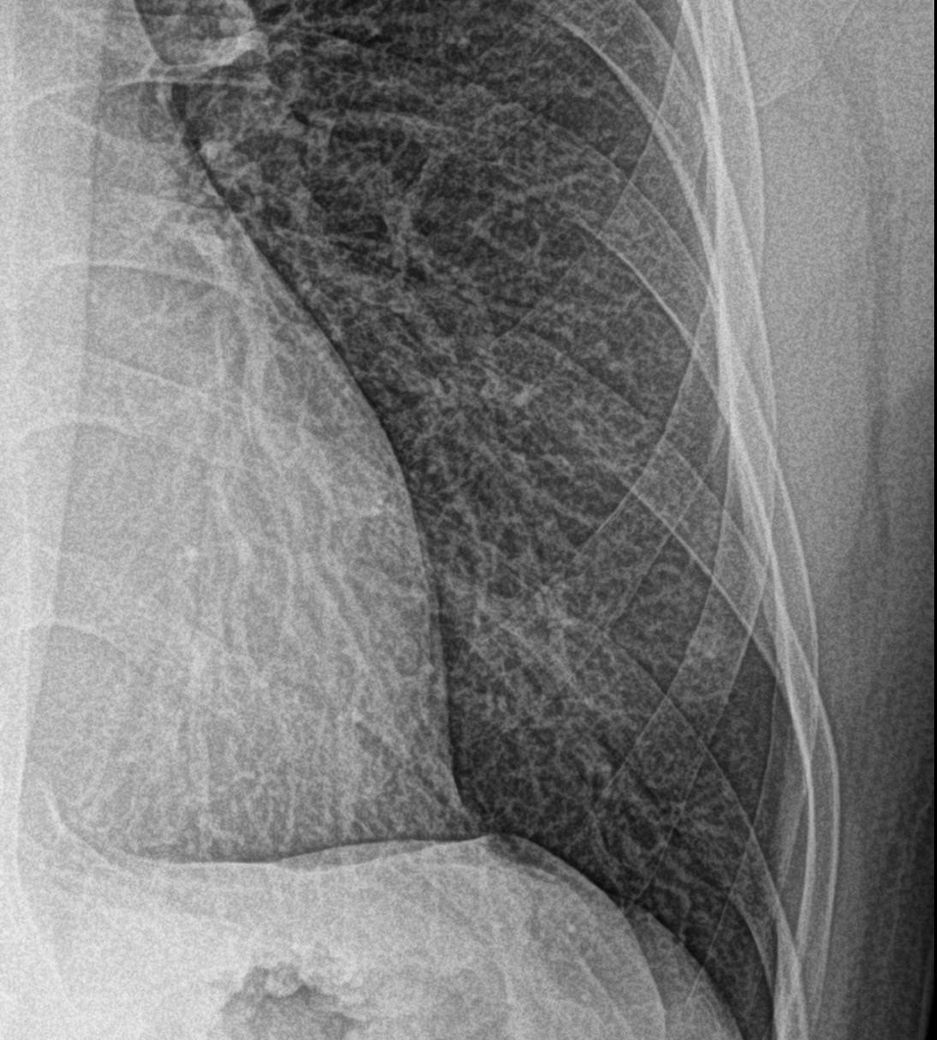

흉부X-RAY 에서 좌하엽 폐결절 소견으로 CT찍고왔습니다.

흉부X-RAY 에서 좌하엽 폐결절 소견으로 CT찍고왔습니다. CT결과를 들으러 20일이나 뒤에 가야하는데 너무 오래거릴네요

엑스레이상 폐결절이 심한가요?

• 1번 째 사진

엑스레이상 좌폐하에 작은 폐결절이 의심되며 1cm 미만의 폐결절로 추정되는데 이러한 크기의 폐결절은 흉부 엑스레이 사진만으로는 폐암의 가능성을 추정하기 어렵습니다. 흡연 여부가 중요한데 비흡연자의 경우 1cm 미만의 폐결절은 폐암 가능성이 낮은 것으로 알려져 있습니다.

올려주신 흉부 방사선 사진에서 결절의 크기가 작아 확인이 어려우므로 걱정되시더라도 CT 결과의 확인이 필요하겠습니다.

• 올려주신 흉부 X-ray 한 장만으로 폐결절의 심각도를 판단하는 것은 제한이 많습니다. X-ray에서 보이는 좌하엽 음영은 실제 결절이 아닐 수도 있고, 혈관 그림자·늑골 겹침·염증 흔적 등으로 과대평가되는 경우도 흔합니다. 특히 폐결절은 크기, 경계, 밀도, 석회화 여부가 중요한데 이런 정보는 X-ray로는 거의 구분이 어렵고 CT가 기준 검사입니다.

일반적으로 CT를 바로 시행했다는 점 자체는 응급성이 높다는 의미는 아닙니다. 수 mm 단위의 작은 결절이거나 양성 가능성이 높아도 CT로 확인하는 경우가 많고, 악성이 의심될 정도라면 보통 결과 설명 일정이 더 앞당겨지거나 추가 검사 안내가 동반되는 경우가 많습니다. 현재 일정이 20일 후로 잡혀 있다는 점은 임상적으로 급한 소견일 가능성은 낮다는 쪽에 무게가 실립니다.

결론적으로 X-ray 한 장만 보고 “심하다”라고 판단할 소견은 아닙니다. 최종 판단은 CT 결과를 봐야 하며, CT에서 크기가 작고 경계가 매끈하거나 석회화가 있으면 대부분 경과관찰로 끝납니다. 반대로 CT에서 추가 조치가 필요하다면 의료진이 보통 더 빠르게 연락을 줍니다.

CT 촬영 당시 조영제를 사용했는지, 흡연력이나 과거 폐질환 병력이 있는지는 결과 해석에 영향을 줄 수 있습니다. 이런 부분도 함께 정리해두시면 결과 설명을 들으실 때 도움이 됩니다.